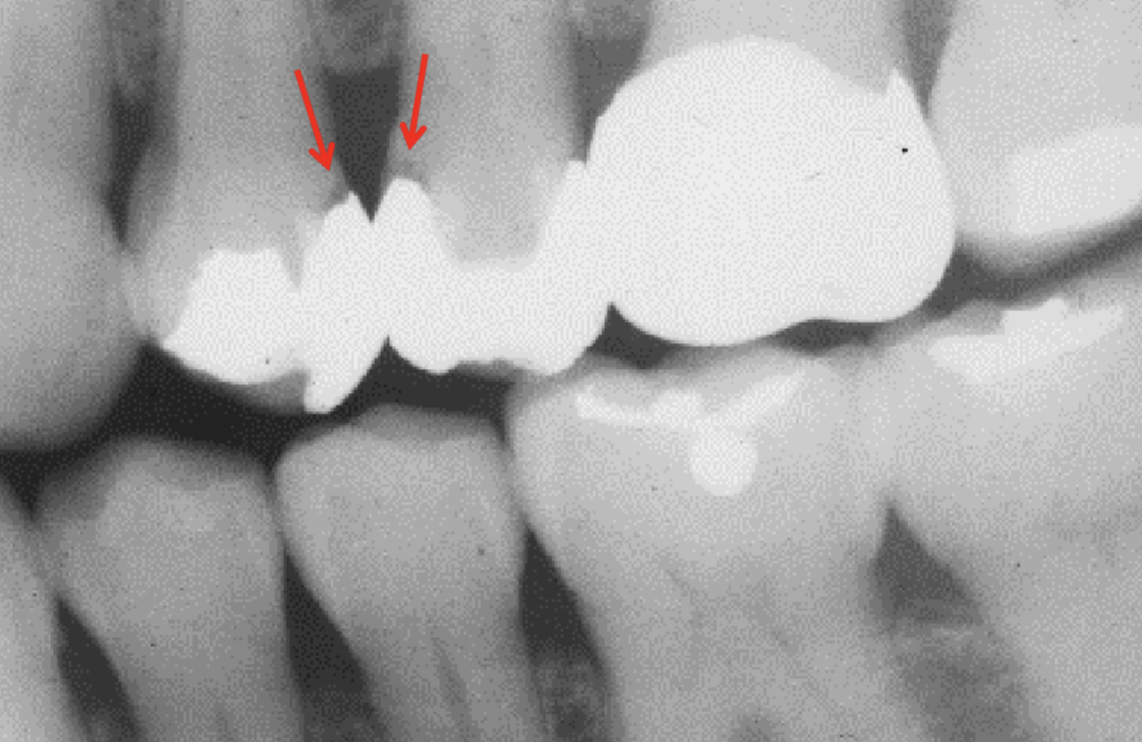

What is going on in the following radiograph?

Severe occlusal caries